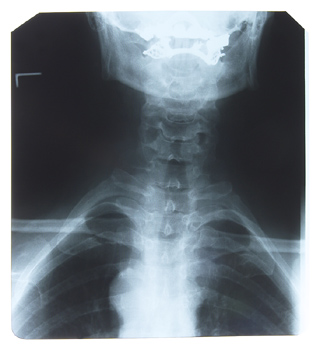

Getting a spinal adjustment is one of those complicated things that doesn’t seem so complicated on the surface. What is it that the chiropractor is really doing? Why do I need to have a chiropractic adjustment, what’s wrong with just twisting my own neck?

I think you’ll agree that if you are trying to move your spine, you have determined that it is either not moving or it has moved out of place, right? If it can go the wrong direction and cause pain and discomfort, then it makes sense that if you move it further out of place you can make it worse. So… how do you know which way to move your vertebrae? The move that I see being performed is a “move everything and hope I get the right one at some point.”

Each vertebrae can move up to sixteen different directions. Do you know which way your vertebra has gone? That’s where the chiropractor comes in. They are trained to determined which way the bone has moved and how to move it back into the correct place. Some of the directions are extremely difficult to accomplish on your own. Chiropractors don’t adjust themselves either!